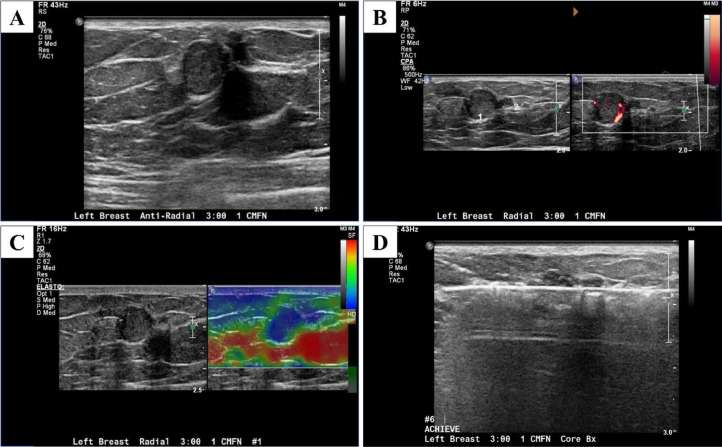

Focused Ultrasound was done to further evaluate these abnormal mammogram findings and the periareolar region of the left breast for the nipple discharge using both a radial approach and an antiradial approach (Fig. 2). This revealed 2 round, circumscribed, isoechoic masses with internal vascularity measuring 10 and 4 mm at 3-o'clock, located 1 cm from the nipple in the area of palpable concern. Elastography was used and showed the masses were hard (Fig. 2).

Fig. 2.

Focused grayscale ultrasound in the left breast in the area of palpable concern showed 2 adjacent 10 mm and 4 mm round, circumscribed, isoechoic masses in the left breast 3: 00 position 1 cm from the nipple (A), which have increased blood flow on the Doppler ultrasound (B) and are hard on the elastography (C). Ultrasound-guided core biopsy with a 12-gauge needle was done in the left breast at 3-o'clock and 1 cm from the nipple (D).

Ultrasound-guided core biopsy was performed (Fig. 2), and a biopsy clip was placed (Fig. 3).